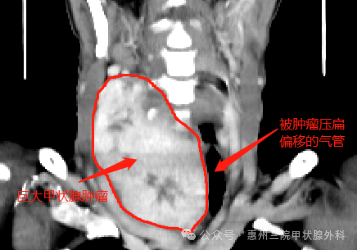

門診醫(yī)生詢問病情后,初步考慮是“肺炎”可能,于是安排了心電圖、頸胸部CT等檢查。結(jié)果出來后,醫(yī)生證實(shí)了自己的診斷,但同時(shí)也發(fā)現(xiàn)了更嚴(yán)重的問題!CT結(jié)果顯示:1.雙肺散在慢性炎癥及纖維灶。2.左肺數(shù)個(gè)實(shí)性結(jié)節(jié)。3.甲狀腺異常改變,考慮結(jié)節(jié)性甲狀腺腫并右側(cè)胸內(nèi)甲狀腺腫形成,大小約105×78×59mm。這相當(dāng)于有一個(gè)成年男性拳頭大小的腫物壓在李阿婆的氣管上。原來,造成她胸悶氣短的“元兇”是結(jié)節(jié)性甲狀腺腫!

李阿婆的頸部CT